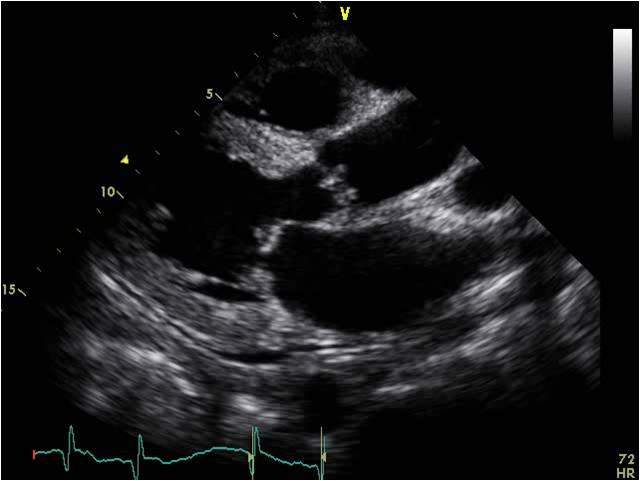

心脏淀粉样变 ECHO:LVH,室壁回声增强,可见颗粒状回声,二尖瓣主动脉瓣增厚,少量心包积液。

心脏淀粉样变 ECHO:LVH,室壁回声增强,可见颗粒状回声, 心包积液。

限制型心肌病ECHO:双房大;右室心尖部闭锁